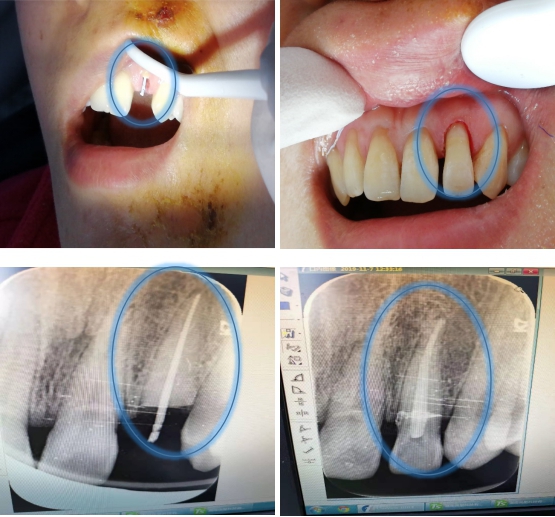

接诊的徐裕国副主任医师检查后发现,患者左上侧切牙折断、松动,牙片显示牙颈部水平折断。通常情况下,处理方法大多需连根拔除,再行义齿修复(假牙)。但徐医生当时考虑,是否可以先做根管治疗,再通过桩钉将两断端拼接。这样一则可以迅速还原牙齿容貌;二则减少痛苦,节省大笔费用。

在与患者充分沟通后,陈女士接受拼接术治疗方案。经过完善的根管治疗,精准的桩钉栓接和断面的超级粘接,将断牙完美复原,取得了良好的效果,患者牙齿修复成功。